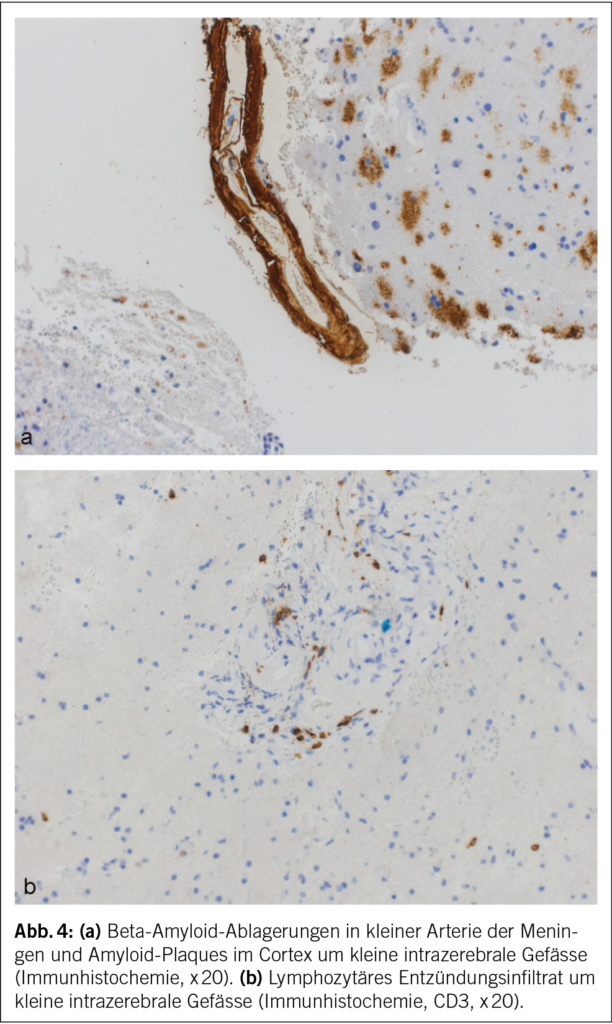

Eine 74-jährige Patientin wurde im Januar 2022 mit seit einigen Wochen fortschreitender Verwirrtheit, Verlangsamung sowie kognitiver Beeinträchtigung aus einem peripheren Spital in unsere Notaufnahme überwiesen. Ausserdem bestand ein progredienter Mutismus, welcher im Rahmen einer Trauersituation nach dem Tod des Ehemannes 1 Monat zuvor aufgrund von Covid-19 angesehen wurde. Die Patientin selbst litt an Covid-19 mit milden Symptomen. Nun zeigte das MRI des Neurokraniums eine ausgedehnte Leukenzephalopathie, ein vasogenes Ödem und mehrere Mikroblutungen (Abb. 3). Die Ergebnisse des Liquors waren negativ für Treponema pallidum und Lyme-Borreliose, ebenso eine Multiplex-PCR für Meningitis-Erreger. Die Immunphänotypisierung im Liquor, welche bei Verdacht auf ein Lymphom durchgeführt wurde, war negativ für B-Zell- und T-Zell-Neoplasien. Eine Bestimmung im Liquor von Beta-Amyloid, Tau-Protein und Phospho-Tau-Protein als Demenzmarker sowie Neurofilament-Leichtketten (NFL) als Marker bei Multipler Sklerose erfolgte nicht. Ebenso wurden die Biomarker GFAP und NFL serologisch nicht untersucht. Es wurde ein EEG angefertigt. Neben moderaten Allgemeinveränderungen und bifrontaler fokaler Verlangsamung fanden sich Epilepsieverdächtige Einzelpotenziale rechtshemisphärisch, welche unter Levetiracetam-Therapie nach 1 Woche abnahmen. Klinisch kam es jedoch noch zu keiner objektivierbaren Verbesserung. Die Patientin erzielte im MoCa-Test 12/30 Punkte, was für eine starke kognitive Beeinträchtigung steht. Schliesslich wurde eine Biopsie des Hirngewebes entnommen. Diese zeigte Veränderungen im Zusammenhang mit der Alzheimer-Krankheit mit Tau-positiven Neuronen, neurofibrillären Tangles und eine grosse Menge an Beta-Amyloid-Plaques sowie Amyloidablagerungen an den Gefässwänden (Abb. 4). Zusätzlich fanden sich subarachnoidal Zeichen einer wenige Tage alten Einblutung. Aufgrund der perivaskulären Entzündung wurde schliesslich eine cerebrale Amyloidangiopathie-assoziierte Entzündung (CAA-RI) als am wahrscheinlichsten angesehen. Eine Therapie mit Methylprednisolon intravenös 1 g/Tag gefolgt von oralem Prednisolon mit 1 mg/kg Körpergewicht wurde eingeleitet. Nach der Entlassung erfolgte eine stationäre neurologische Rehabilitation. Hier kam es zu einer klinischen Verbesserung mit jedoch relevanten Einschränkungen in Bezug auf die täglichen Routinen und das Kurzzeitgedächtnis. Die Prednisolon-Dosis wurde langsam reduziert.

Die Amyloidablagerungen sind bei einem Teil der Patienten mit einer Entzündung der Gefässwand vergesellschaftet, was schliesslich zu einem multifokalen Marklagerödem führt. Insgesamt zeigen diese Veränderungen im MRI ein typisches Bild, welche für die Diagnosestellung einer CAA-RI wesentlich sind. Die Veränderungen lassen sich vor allem in der FLAIR-Sequenz (fluid attenuated inversion recovery) und bei der SWI (Suszeptibilitätsgewichtete Bildgebung) feststellen (2, 3). Dazu gehören Mikroblutungen, eine kortikale superfizielle Siderose und eine asymmetrische fleckförmige oder konfluierende Leukenzephalopathie, welche den angrenzenden Kortex und das subkortikale Marklager miteinbeziehen können. Ebenfalls kann sich als Zeichen der entzündlichen Reaktion ein vasogenes Ödem in der ADC- (apparent diffusion coefficient) Wichtung präsentieren (2, 4, 5). Es wurden die sogenannten modifizierten Boston-Kriterien entwickelt, welche auf eine gute Sensitivität und Spezifität geprüft wurden (6) (Tab. 1) und bei der Diagnosesicherung helfen. Zusätzliche klinische Diagnosekriterien sind ein akuter/subakuter Symptombeginn, Alter über 55 Jahre, Symptome wie Kopfschmerzen, Wesensveränderungen, kognitive Defizite oder fokal neurologische Defizite oder epileptische Anfälle. Andere Ursachen (z. B. infektiös oder paraneoplastisch) müssen ausgeschlossen werden. Sind alle diese Kriterien erfüllt, gilt eine CAA-RI als wahrscheinlich. Zur definitiven Diagnosesicherung wird eine histologische Bestätigung im Rahmen einer Autopsie benötigt, wobei sich neben frischen und alten Ischämien und Einblutungen auch entzündliche, perivaskuläre Veränderungen ohne Gefässbeteiligung finden lassen. Hier kann eine Unterscheidung zur Beta-Amyloid-assoziierten Angiitis (ABRA) gemacht werden, welche ausgeprägtere vaskulitische Veränderungen und fibrinoide Gefässwandnekrosen zeigt. Diese erheblichen Zerstörungen des Hirnparenchyms direkt durch invasive zytotoxische T-Lymphozyten und indirekt durch vaskulitische oder begleitthrombotische Gefässverschlüsse bedingen eine stärkere Immunsuppression als bei der CAA-RI. Teils wird in der Literatur jedoch die ABRA synonym zur CAA-RI genannt. Ob eine Histologie zur Diagnosestellung einer CAA-RI immer zwingend ist, steht aktuell immer noch zur Diskussion. Eine genaue Diagnose hat jedoch teils therapeutische Konsequenzen. Vor allem bei fehlendem Therapieansprechen sollte eine Biopsie angestrebt werden.